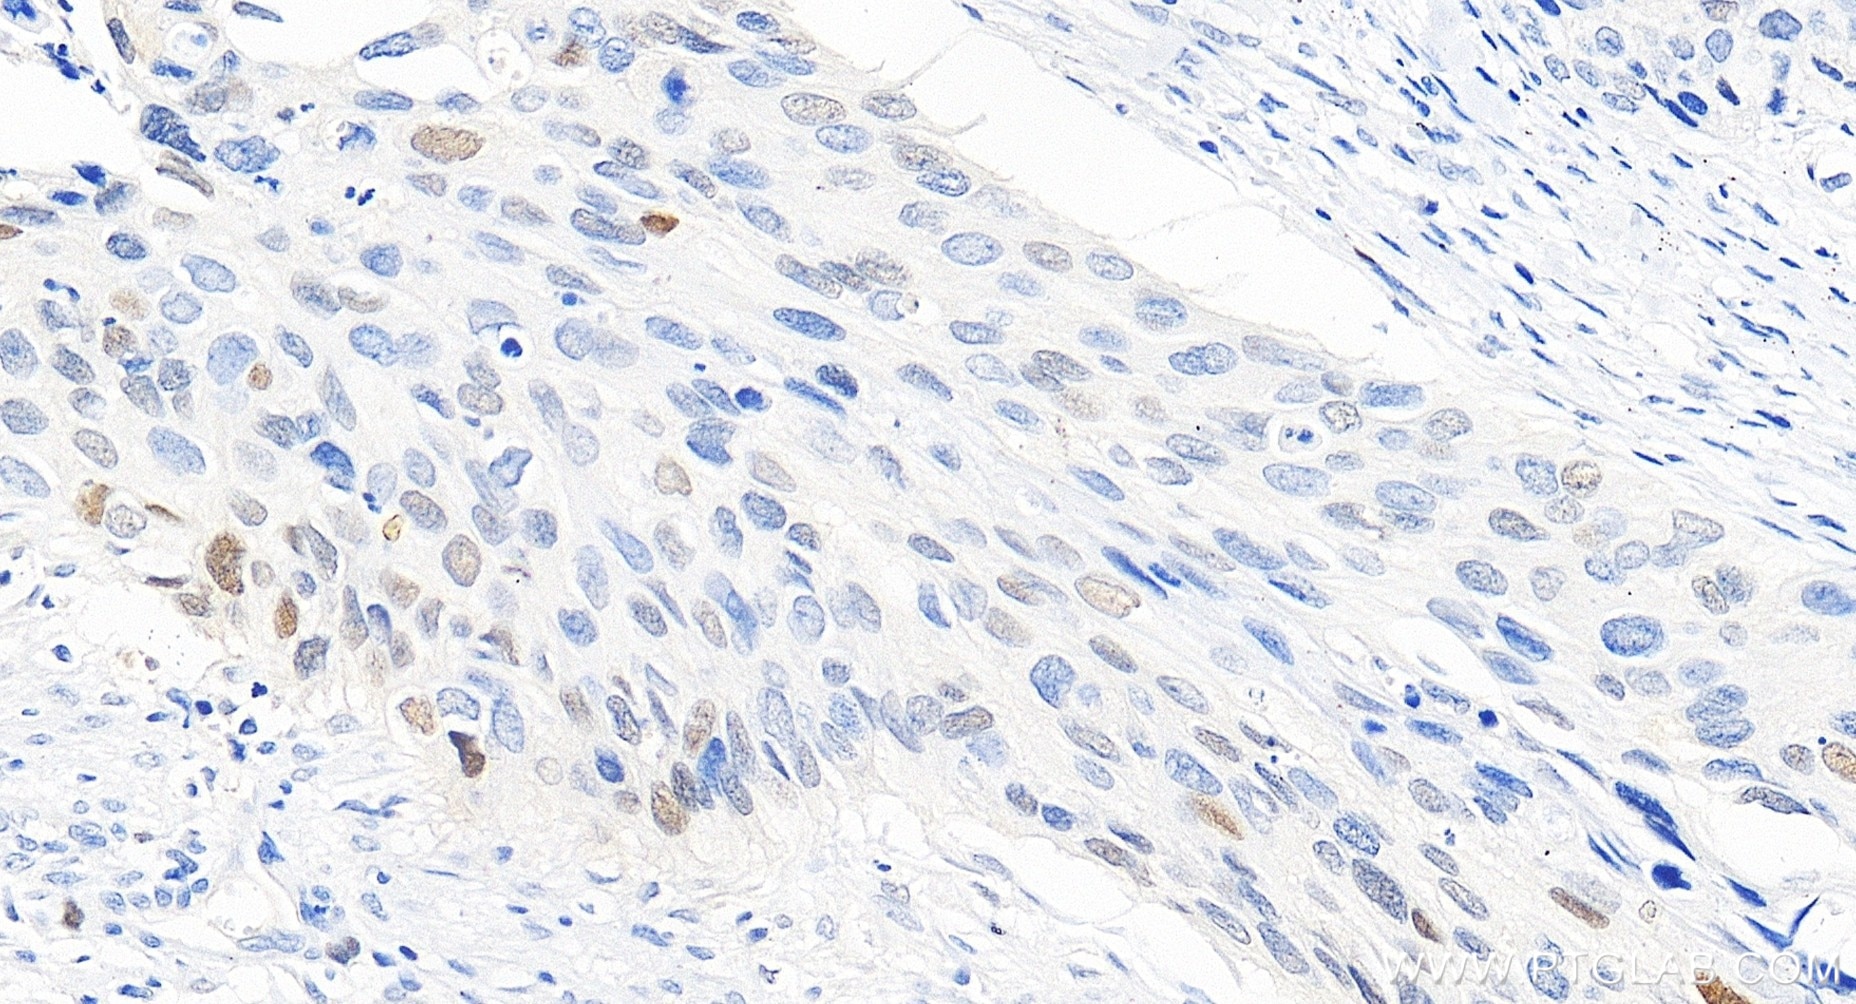

| Positive IHC detected in | human cervical cancer tissue, human colon cancer tissue, human tonsillitis tissue Note: suggested antigen retrieval with TE buffer pH 9.0; (*) Alternatively, antigen retrieval may be performed with citrate buffer pH 6.0 |

| Immunohistochemistry (IHC) | IHC : 1:200-1:800 |

82669-2-RR targets P21 in WB, IHC, IF/ICC, IP, ELISA applications and shows reactivity with human samples.